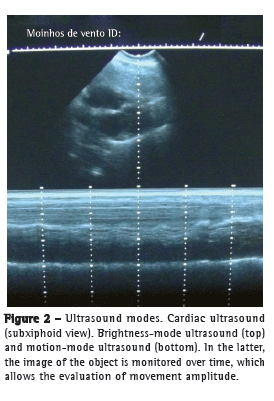

The way in which the reflected signals are processed determines image formation. When brightness-mode (B-mode) ultrasound is used, the amplitude of energy is shown as dots of varying intensity, which allows conventional two-dimensional image formation; when motion-mode (M-mode) ultrasound is used, the image of a given object is monitored over time (Figure 2).(5)